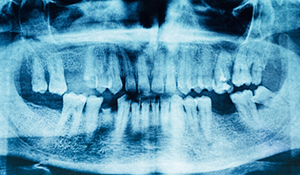

- High-Powered Dental Technology for Accurate Imaging

You will begin with a scheduled consultation with Dr. Parry to determine your eligibility for treatment. If he believes you are a good candidate, he will make sure to capture scans, photos, and images of your mouth so that a more detailed impression is created. Once this is accomplished, he will send you home.